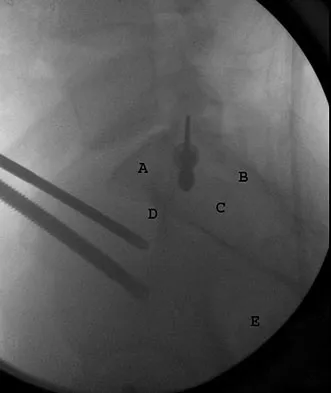

Question 19

Figure 30 shows an axial cross section of extensor tendon anatomy in zone 7 of the wrist. What letter best depicts the location of the posterior interosseous nerve?

Explanation